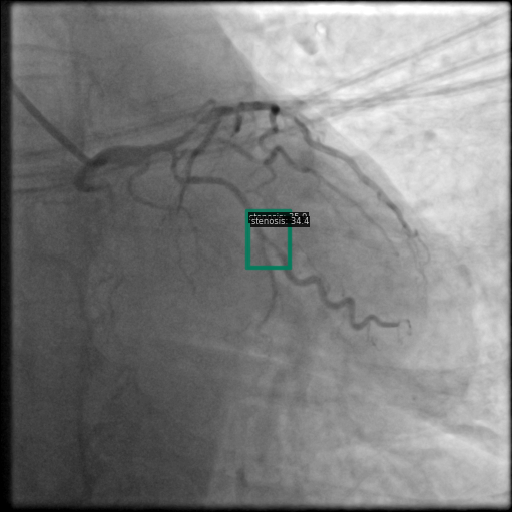

Figure 1 shows sample images from the ARCADE dataset with annotations for stenosis detection. The annotations highlight regions of arterial narrowing, providing ground truth data for training and evaluating object detection models.

To further assess the detection performance, qualitative results for three test images are presented in Figure 2. The first column shows the original images with ground truth annotations. The second, third, and fourth columns depict detections from DINO-DETR, Grounding DINO, and YOLO, respectively.

(a) Original (b) DINO-DETR (c) Grounding DINO (d) YOLO

The qualitative comparison in Figure 2 reinforces the trends observed in the quantitative evaluation. DINO-DETR produced fewer detections, occasionally missing relevant stenotic regions, consistent with its conservative detection strategy aimed at minimizing false positives [6]. Grounding DINO, although capable of identifying more regions, sometimes resulted in cluttered predictions due to over-detections [7]. YOLO provided a reasonable trade-off by effectively capturing anatomical structures while maintaining relatively high confidence scores and clear visualizations [5].